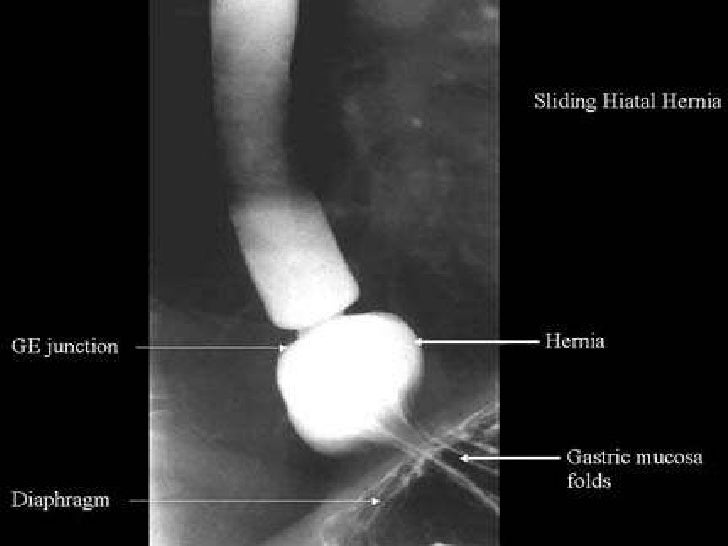

Sliding Hiatal Hernia X Ray . A sliding hiatal hernia may also be. tests that can diagnose a hiatal hernia include: uncomplicated sliding hiatus hernias are treated symptomatically with medical therapy, although some patients. (left) graphic outlines the surgical classification of hiatal hernias (hh). in sliding hiatal hernias, the ge junction migrates above the diaphragm secondary to increased laxity of the phrenoesophageal.